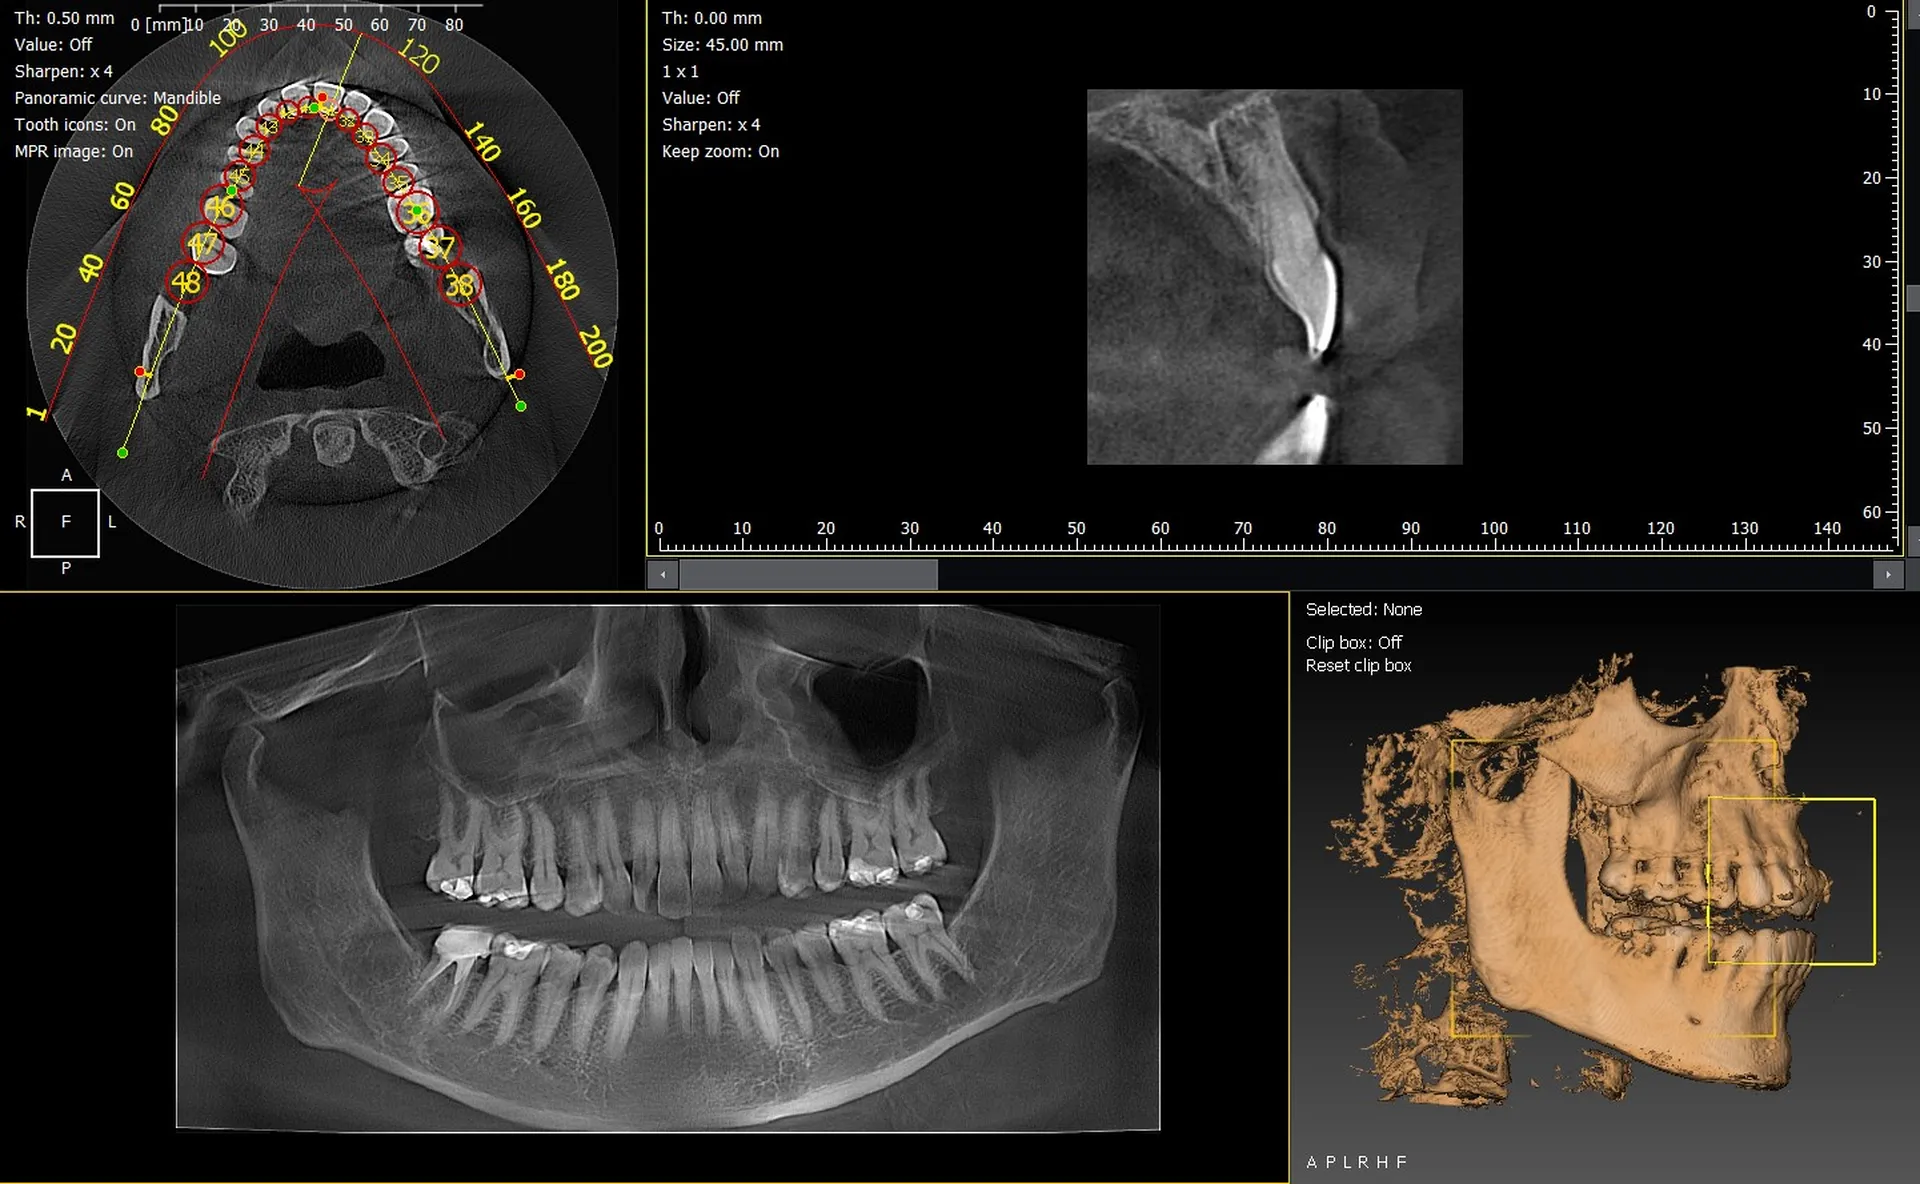

Les cabinets dentaires d’Aubagne et du département des Bouches-du-Rhône (13) modernisent leur plateau technique grâce à des solutions d’imagerie 3D fiables, performantes et adaptées aux besoins cliniques actuels. Les panoramiques CBCT 3D VistaVox de Dürr Dental et l’Owandy I-Max 3D figurent parmi les appareils les plus avancés, offrant une précision diagnostique remarquable et une qualité d’image de très haut niveau.

Owandy I-Max : compact, polyvalent et simple d’utilisation

L’Owandy I-Max 3D se démarque grâce à :

• son encombrement réduit, idéal pour les cabinets urbains,

• ses protocoles rapides en 2D/3D,

• sa qualité d’image précise,

• sa prise en main intuitive.

Un appareil particulièrement adapté aux praticiens d’Aubagne souhaitant optimiser l’espace tout en renforçant la performance diagnostique.